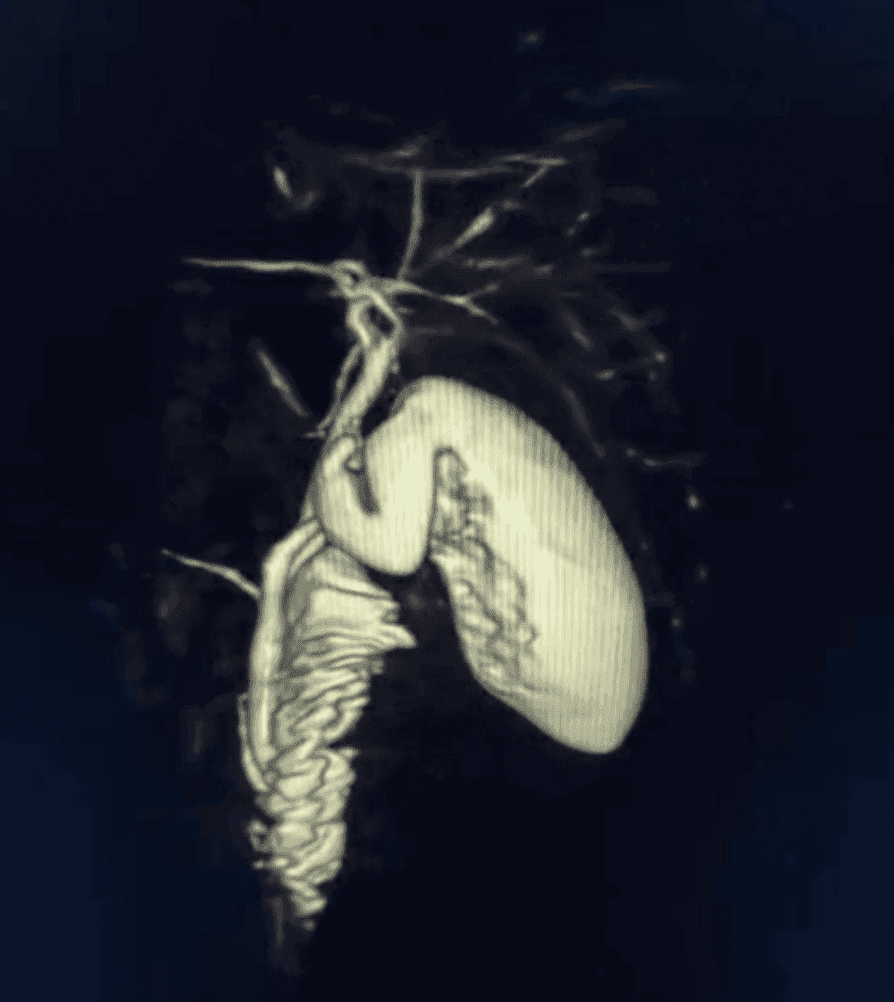

Tecnología 3D para estudios especializados

Realizamos estudios avanzados como colangioresonancia (vías biliares) y protocolos de alta definición. Si tu médico solicita contraste, te orientamos con preparación y seguridad.